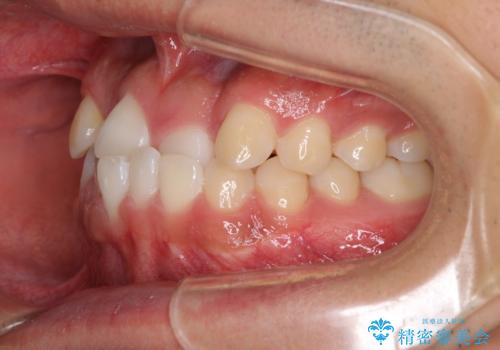

今後はすり減ってしまった歯の形をセラミッククラウンで改善したいとのことで、クロスバイトが改善し咬みやすくなった時点で装置を外すこととしました。

1年で治療を終えることができ、患者様には大変満足していただきました。